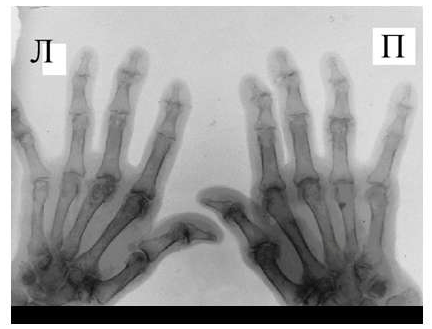

Рис. 6 Сужение суставной щели, остеофиты и субхондральный остеосклероз, кистовидные просветления костной ткани, костные дефекты (псевдоэрозии), деформации эпифизов костей при остеоартрозе.

Среди обязательных диагностических критериев для верификации остеоартроза необходимо выделить сужение суставной щели, наличие остеофитов и субхондрального остеосклероза, вспомогательными являются кистовидные просветления костной ткани, костные дефекты (псевдоэрозии), деформации эпифизов костей (рис. 6), подвывихи и вывихи суставов, синовиты и обызвествленные хондромы.

Оценка рентгенологических стадий остеоартроза проводится по критериям, предложенным J.Kellgren, J. Lawrence в 1957 году.